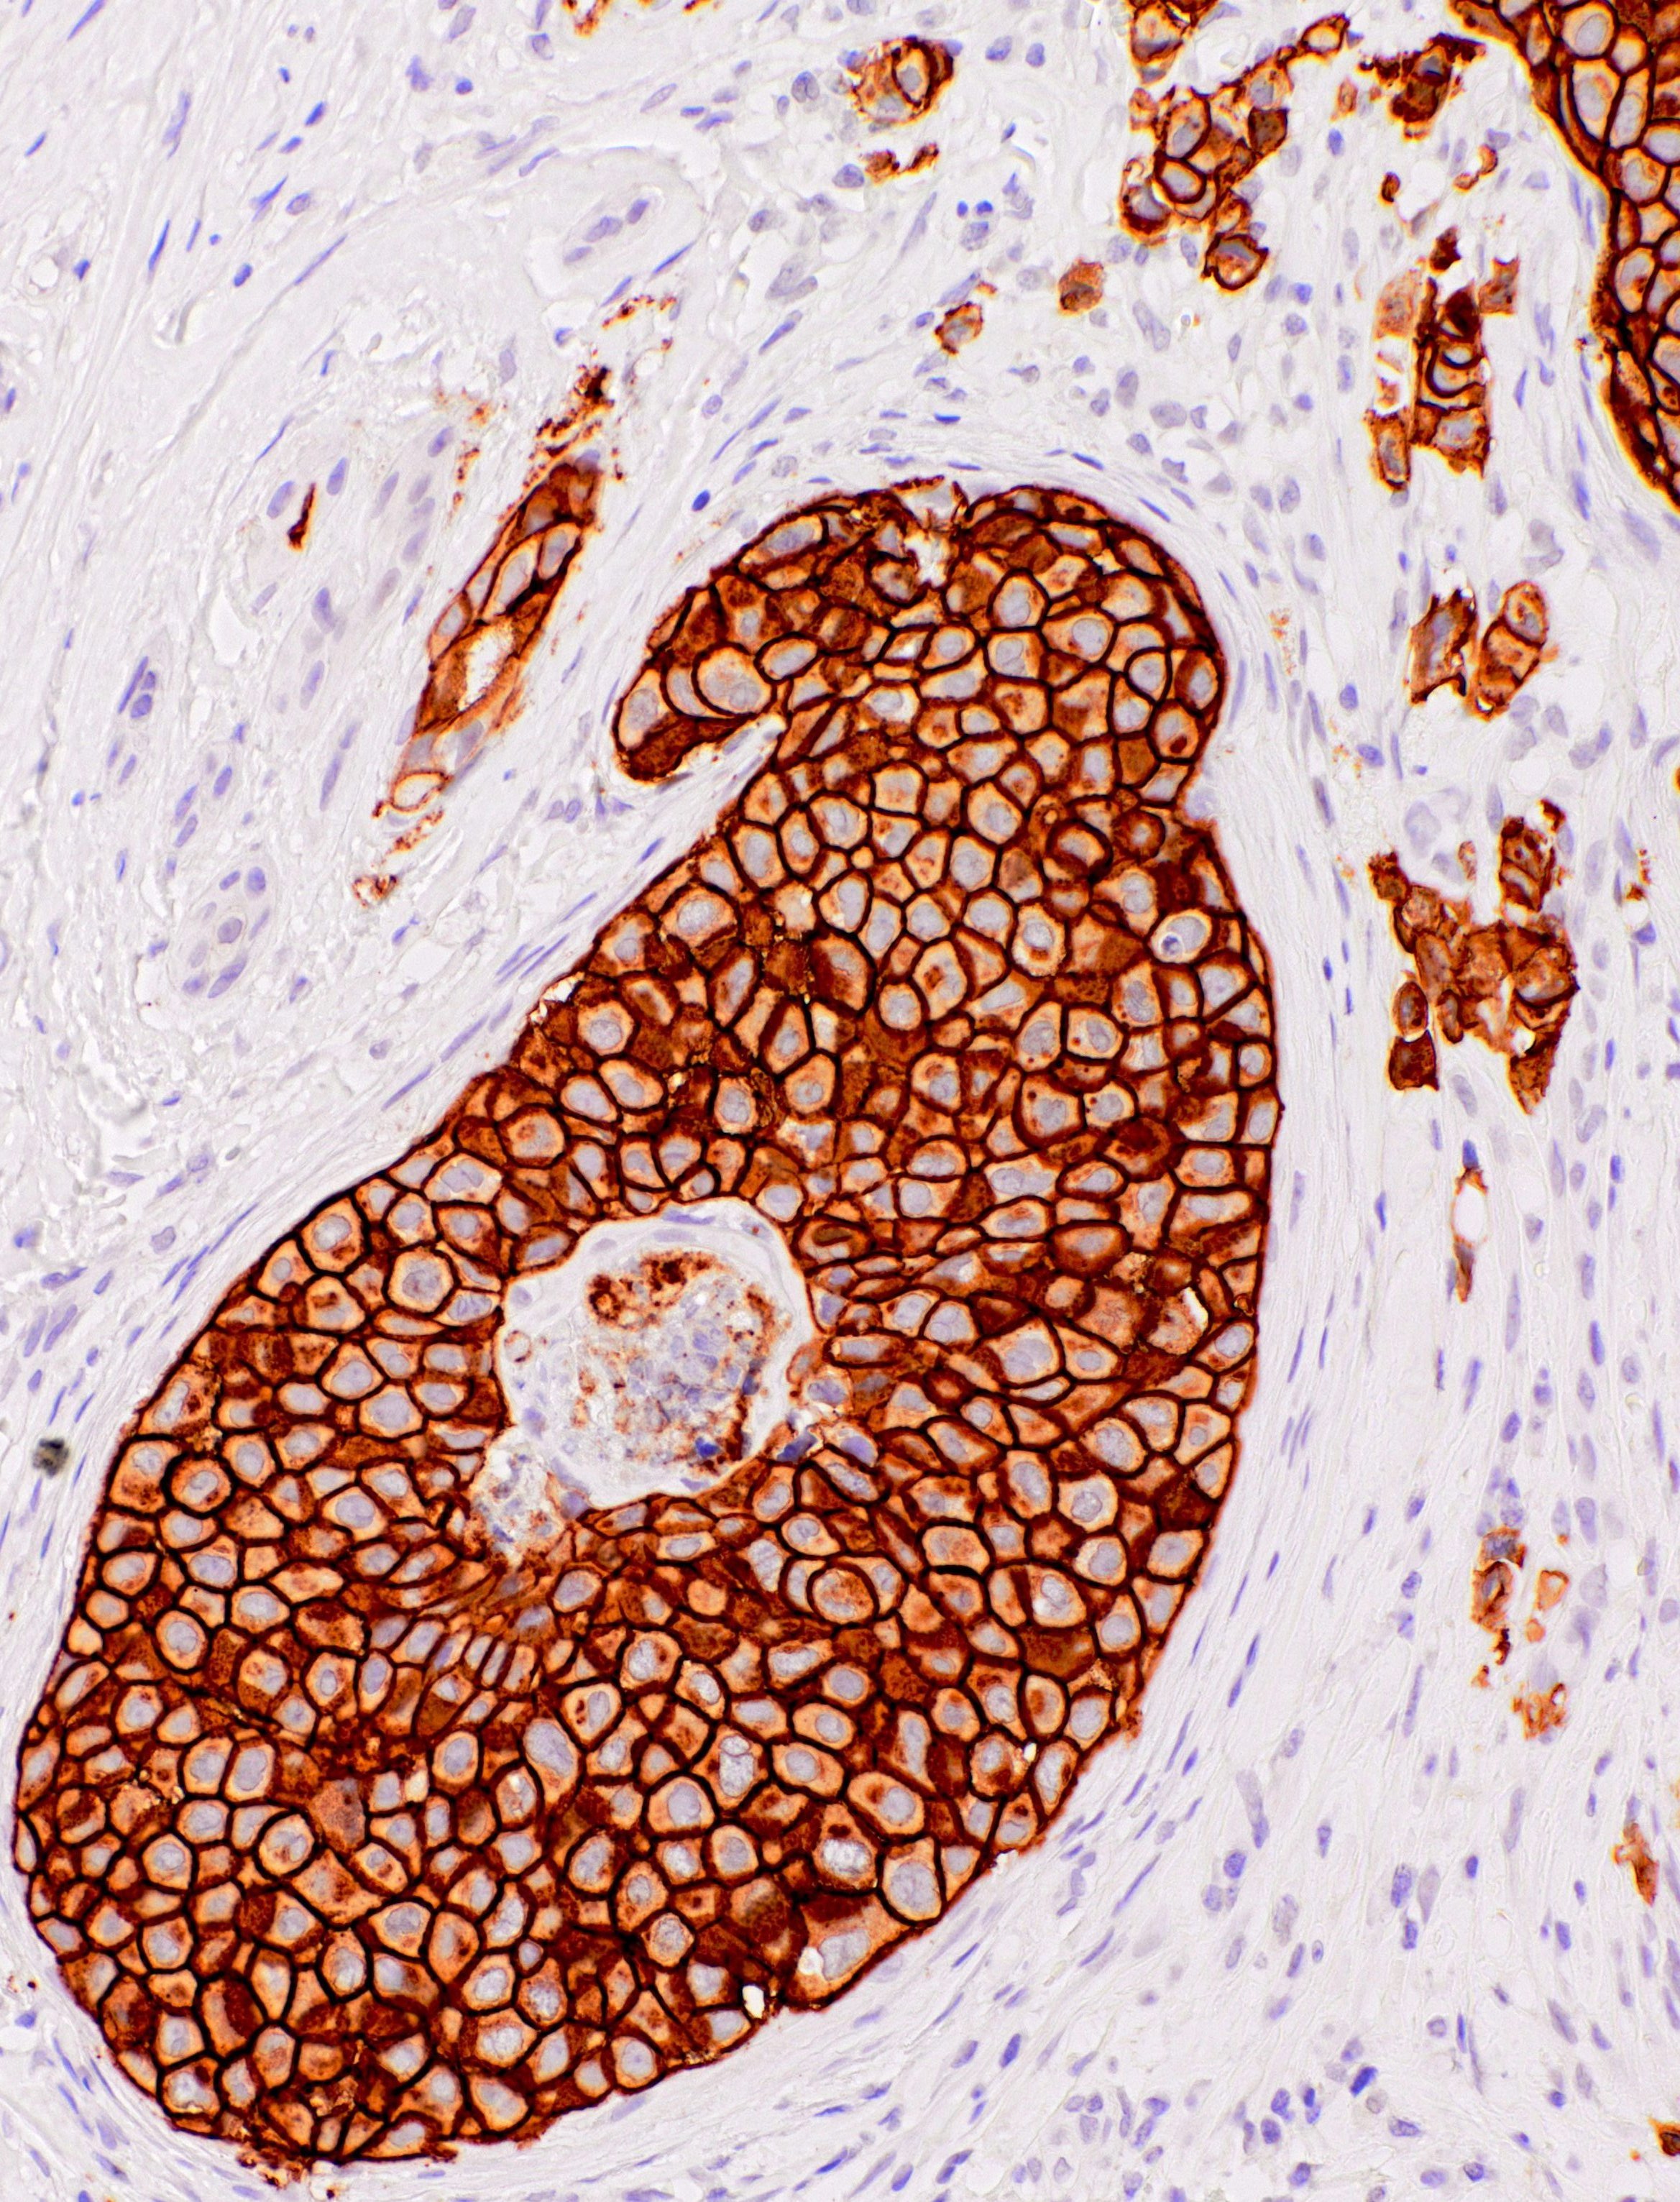

[Genomeme] HER2/neu

CAT. NO. IHC012-1

IHC012

POSITIVE CONTROL:

Breast Carcinoma

The HER2/neu (c-erbB-2) proto-oncogene is a transmembrane receptor tyrosine kinase that is clinically indicated in a number of carcinomas. Overexpression of the c-erbB-2 protein has been associated with ductal breast cancer, as well as pulmonary and gastric adenocarcinomas. A correlation between HER2 and p53 has also been documented, as overexpression of both proteins has been associated with early invasion and metastasis in bladder cancer.